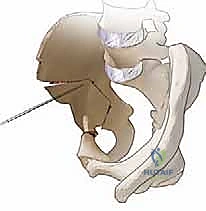

الخطوة الثالثة: القطع العظمي المتعدد (The Osteotomies)

هنا تكمن عبقرية الجراحة. يقوم الدكتور هطيف بإجراء سلسلة من القطوعات العظمية الدقيقة باستخدام أزاميل ومناشير جراحية متخصصة:

1. قطع عظمة الإسك (Ischial Cut): الجزء السفلي والخلفي من الحوض.

2. قطع عظمة العانة (Pubic Cut): الجزء الأمامي من الحوض.

3. قطع عظمة الحرقفة (Iliac Cut): الجزء العلوي من الحوض.

هذه القطوعات تحرر تجويف الحُق بالكامل عن باقي الحوض، مع الإبقاء على الحلقة الحوضية الخلفية سليمة لضمان استقرار الحوض أثناء المشي بعد العملية.